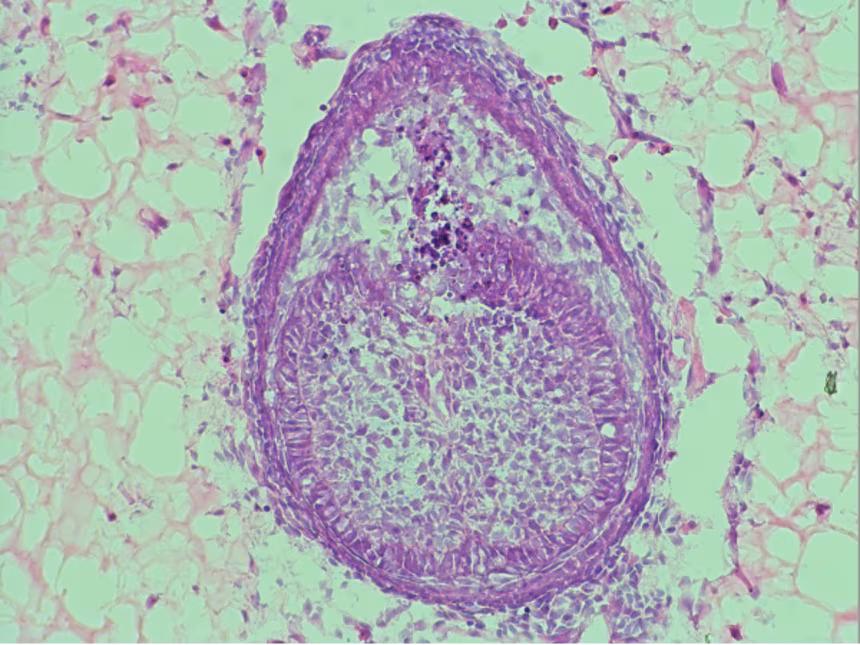

Учёные пытаются вырастить человеческие зубы. Есть успехи

Исследователи из Королевского колледжа Лондона разработали новый материал, который помогает выращивать зачатки зубов почти как в живой челюсти. Об этом пишет CNN.